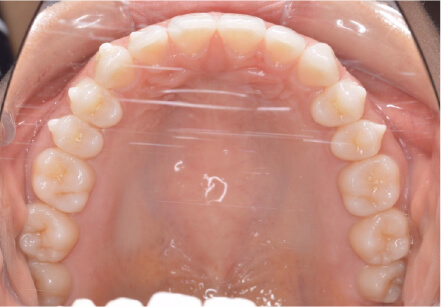

叢生の症例

41歳

女性

相談内容

正中がズレている。傾いている歯がある。

カウンセリング・診断結果

叢生・アレルギーなし・ext、IPR、アタッチメント、ミニスクリュー、ゴム掛け承諾

治療内容・方法

全額アライナー矯正・左下7セラミックはそのまま進めていく

術後の経過・現在の様子

クリアライナー使用

治療のリスク

痛み・歯根吸収・歯肉退縮・虫歯・後戻り

費用・治療期間

880,000円、1年9ヶ月